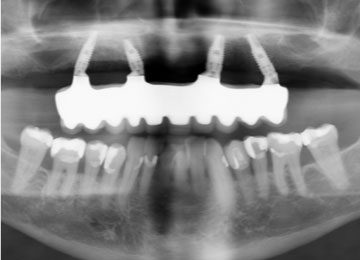

Имплантация зубов: фото "До" и "После"

Фото ДО

Фото ПОСЛЕ

Наведите для просмотра

All-on-4